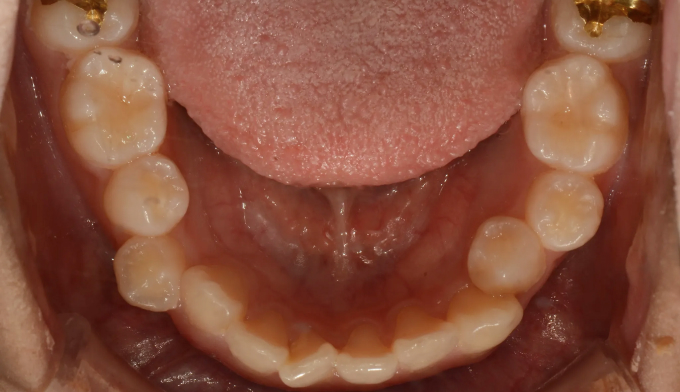

매우 어린나이에 1차교정을 진행했다고 합니다.

1차교정을 한다고 2차교정을 안하게 되지는 않습니다. 오히려 잘못된 1차교정, 성장교정은 2차교정을 더 어렵게 만들기도 합니다.

이번 케이스에서는 덧니가 심하고 공간이 매우 부족하지만, 입의 크기가 작고 입술이 얇은 편이었기 때문에 발치 없이 교정하기로 계획하였습니다.